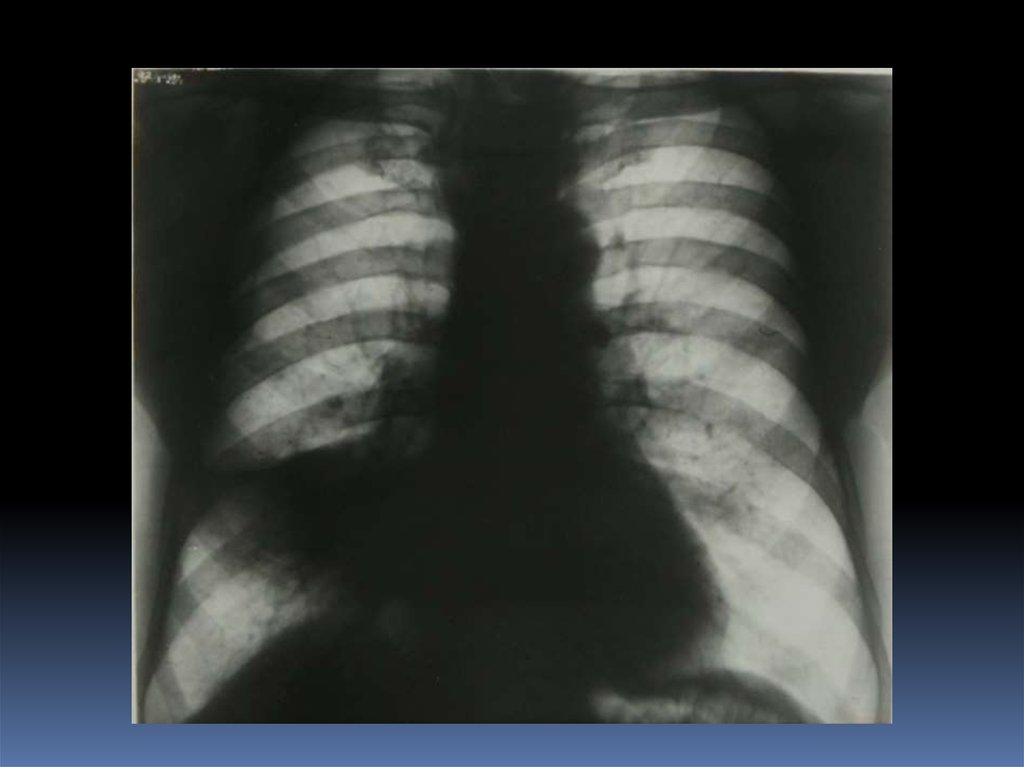

5. Проведение рентгеноскопического исследования раненого.

6. Проведение рентгенографического исследования раненого.

7. Виды травматического повреждения грудной клетки:

пневмоторакс;

гемоторакс;

гемопневмоторакс;

внутрилегочные гематомы;

дисковидные ателектазы;

посттравматические пневмонии.